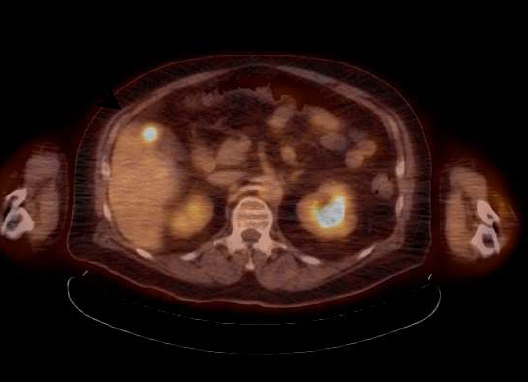

Proton Therapy Radiation X-Ray Liver Metastases

February 6, 2014 — Initial results from a research study reveal that proton radiation therapy can successfully treat metastases to the liver. The research is being conducted at Loma Linda University Medical Center’s (LLUMC) James M. Slater, M.D., Proton Treatment and Research Center.

Gary Yang, M.D., professor of radiation medicine and head of the gastrointestinal service in the Department of Radiation Medicine at LLUMC, is principal investigator of “Stereotactic Body Proton Therapy for Liver Metastases.” The study explores management of liver metastases through non-invasive proton therapy. The therapy is given in higher doses than have previously been used with conventional X-ray therapy.

“Typically invasive open surgery and chemotherapy have been the two main options for controlling liver metastases; but due to patients’ immune systems being compromised or because they are weak, aged and/or frail, many cannot withstand open surgery,” Yang said. “That is what makes our study and the potential benefits of proton therapy so important. We are in Phase 1 of the study, and our initial results are looking promising. Thus far our patients are showing significant tumor reduction without adverse side effects.”